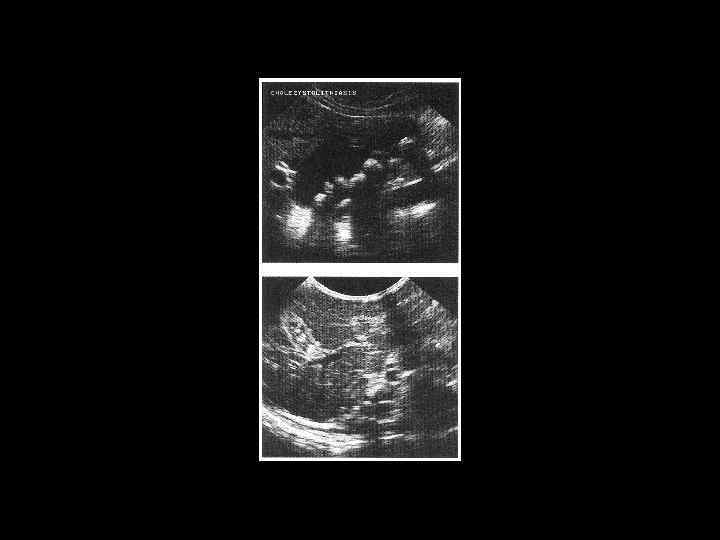

АКТУАЛЬНЫЕ ВОПРОСЫ РЕНТГЕНОЛОГИИ ЛУЧЕВАЯ ДИАГНОСТИКА ЗАБОЛЕВАНИЙ ЖЕЛЧЕВЫДЕЛИТЕЛЬНОЙ СИСТЕМЫ Желчекаменная болезнь УЗ семиотика